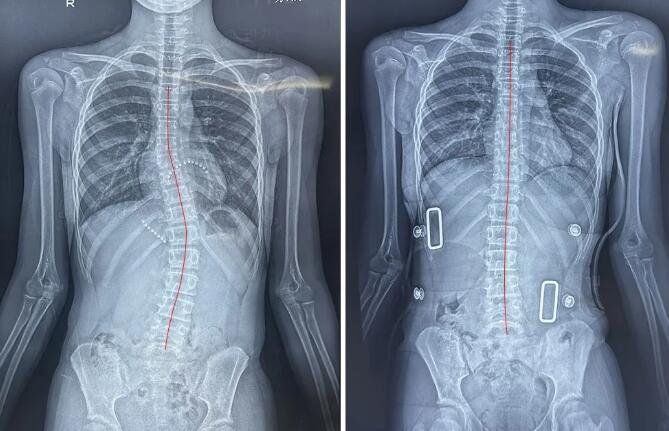

青春期女生调整前(左图)、8节调整课后(右图)